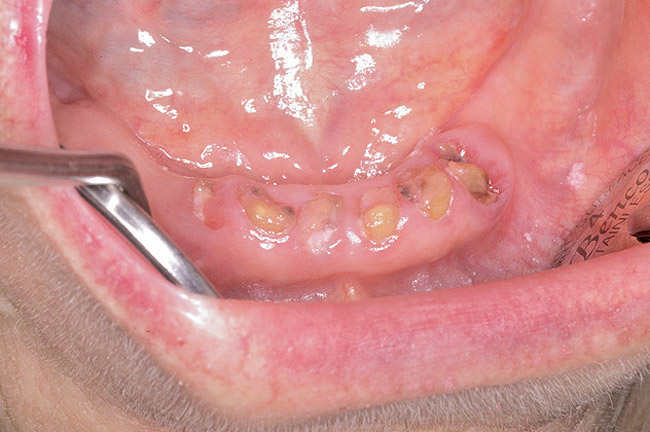

For patients on IV bisphosphonates, after bone is exposed, it is almost impossible to cover.15 Most cases worsen if surgical intervention is performed. Most patients must simply deal with the exposed bone and keep it clean so that bacterial infection does not occur. Figure 2 and Figure 3 show a postmetastatic prostate cancer patient with exposed bone. The treatment plan for this patient was to make a soft-lined denture that would not put pressure on the exposed bone and to check for bacterial infection on a routine basis.

Figure 2  Post-metastatic cancer patient with BRONJ in the lower right quadrant and in the lower left quadrant.

Figure 2

Figure 3  Post-metastatic cancer patient with BRONJ in the lower right quadrant and in the lower left quadrant.

Figure 3